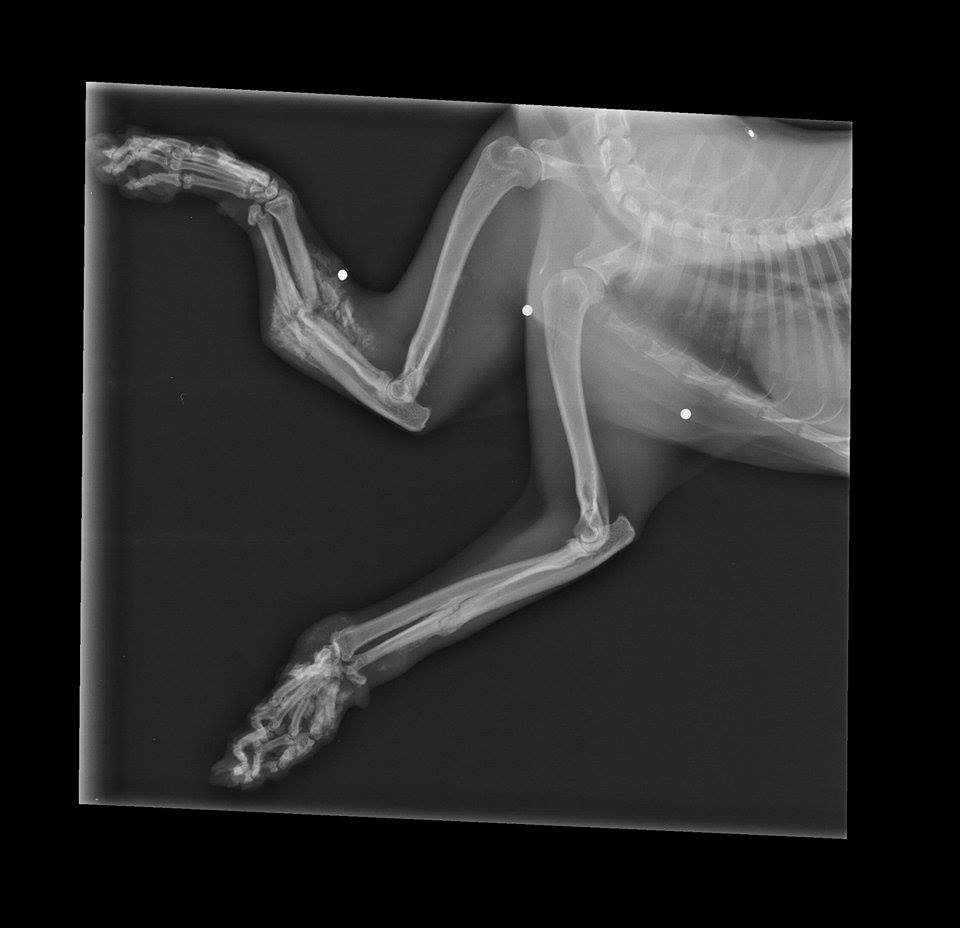

The next day, Copper's appointment at Adrian Animal Clinic revealed the extent of his injuries. X-rays were taken to view the damage and we couldn't believe our eyes. Both paws had several severe fractures and his front left paw had been crushed to point of no return. To make matters worse, x-rays also revealed three BBs or bird shot within his front legs as well. We still had no clue what caused this much damage, but it was beginning to look intentional. Our hearts broke for this poor beautiful, sweet creature.

Upon examination, the veterinarian revealed the bad news. Because of the severity of all of Copper's fractures, treatment through splinting or amputation didn't appear to be viable options. Humane euthanasia was recommended because a quality life did not seem possible with this kind of damage.